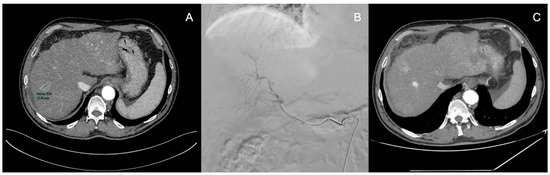

3.3. Transarterial Radioembolization (TARE)

4.2. Transarterial Chemoembolization (TACE)